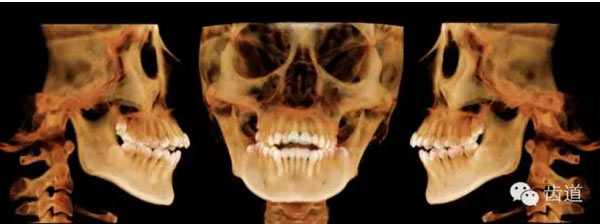

下頜后縮為主要特征的骨性II類,高角,前牙開(kāi)合,上前牙略唇傾,雙側(cè)下頜升支及髁狀突不對(duì)稱,右側(cè)較左側(cè)粗壯,左側(cè)髁狀突外斜面曾有吸收,但現(xiàn)骨白線與皮質(zhì)骨已比較連續(xù),上呼吸道正常。上

頜第三磨牙牙冠較小。

顏面軟組織:面部左右不對(duì)稱,頦部右偏,凸面型,上下唇較厚、略前突,鼻唇角較小,頦唇溝淺,下頜后縮,頦肌緊張,頦部形態(tài)不良

牙與牙弓:25腭側(cè)完全錯(cuò)位導(dǎo)致26前移,上牙列重度擁擠,下牙列中度擁擠,上牙弓尖圓形,下牙弓卵圓形,第三磨牙牙胚存,18與28牙冠較小且形態(tài)不良

橫向:上下牙弓寬度不匹配,下牙弓寬度較上牙弓大,左側(cè)自第一磨牙開(kāi)始至側(cè)切牙均為反合。上牙列中線左偏,下牙列中線右偏。

矢狀向:安氏II類,骨性II類,下頜后縮,上前牙唇傾

垂直向:高角,垂直生長(zhǎng)型,前牙開(kāi)合

骨性II類,高角

安氏II類,牙列擁擠,中線不齊

前牙開(kāi)合